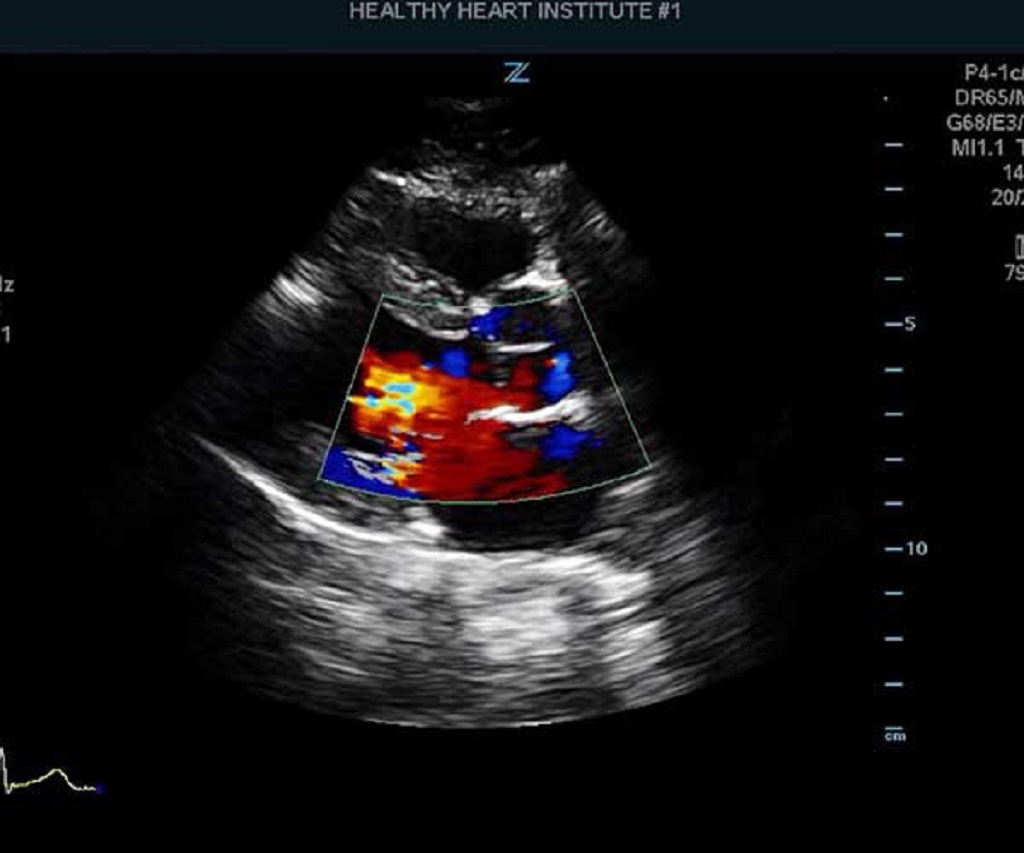

A reliable Echo Cardiogram services in Dindigul, our advanced facility is here to meet your heart health needs. An Echo Cardiogram (Echocardiography) is a non-invasive, painless imaging test that uses ultrasound waves to create detailed images of your heart. This vital diagnostic tool helps assess heart function, detect structural issues, and monitor existing heart conditions.